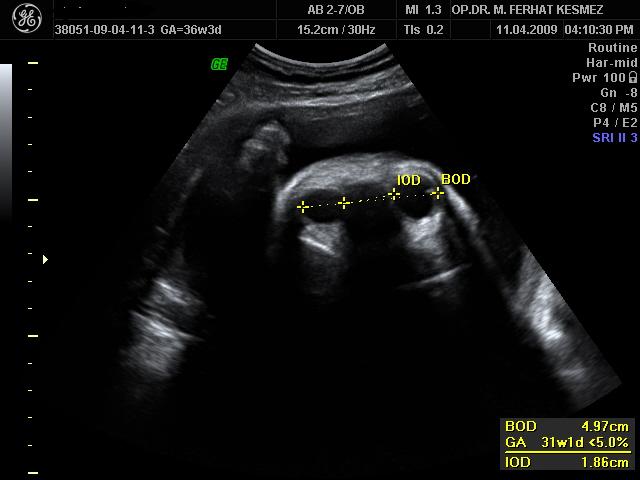

Ultrason Ölçümleri